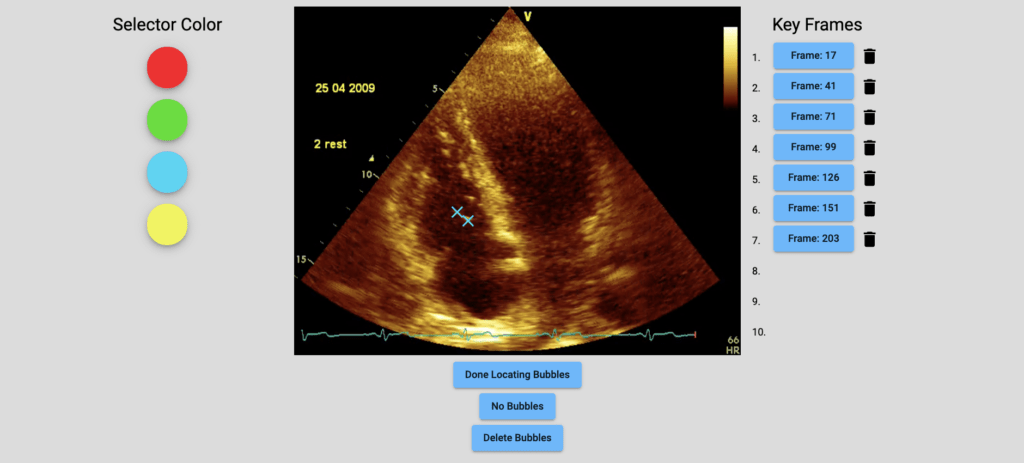

With support from Divers Alert Network, the ultrasound lab at the University of North Carolina (UNC) is experimenting with artificial intelligence (AI) to personalize decompression procedures for divers. Ultrasound imaging can be used to observe nitrogen bubbles circulating in the body after a dive. These bubbles are a marker of decompression stress and can sometimes result in decompression sickness. Observing these bubbles can help us understand individuals’ susceptibility to decompression sickness. Using AI to locate these bubbles in ultrasound videos of the heart will allow us to study how the quantity of bubbles varies in divers at several time intervals postdive.

To build and train an AI to locate bubbles requires a large database of rated post-dive ultrasound videos — many more than our team alone can rate. That is why we are asking for volunteers to help build this database with us by identifying (clicking) bubbles in the videos we’ve uploaded to DecoBubbles.com. We have developed this website so volunteers from around the world can come together and aid us in this first-of-its-kind crowdsourcing campaign.